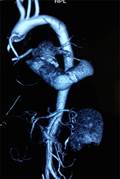

Khó khăn lớn nhất gặp phải khi thực hiện phẫu thuật cho bệnh nhân là không có vật liệu tiêu chuẩn để làm cầu nối. Đó là bộ vật liệu bao gồm ống nối cho mỏm tim, van tim nhân tạo và ống mạch nhân tạo. Các vật liệu này được thiết kế riêng cho phù hợp với việc luồn vào mỏm thất trái và đường đi của nó đến động mạch chủ xuống để không làm hẹp các miệng nối, đoạn gấp khúc và đảm bảo dẫn lưu đủ cung lượng tim [4]. Hiện ở Việt Nam chưa có bộ sản phẩm này trên thị trường. Để giải quyết vấn đề trên, chúng tôi sử dụng ống mạch nhân tạo số 27 để nối với mỏm thất trái, nối một ống mạch nhân tạo khác có gắn van (đầu ngoại vi) vào động mạch chủ xuống đoạn ngang mỏm tim. Sau đó hai đoạn này được nối lại với nhau để tạo thành một cầu nối tắt có van cho dòng máu di chuyển một chiều từ mỏm thất trái xuống động mạch chủ (Hình 4c,d,e,f,g). Lý do để chọn đoạn mạch có cỡ lớn như vậy là đề phòng trường hợp gấp khúc cầu nối dẫn đến gây hẹp và dẫn lưu không hết thể tích tống máu của thất trái. Kết quả chụp cắt lớp vi tính đa dãy đầu dò sau mổ cho thấy vẫn có tình trạng gấp khúc cầu nối trước và sau van nhân tạo (Hình 5) nhưng trên siêu âm thì chênh áp qua các chỗ này là không đáng kể cho thấy việc lựa chọn vật liệu là phù hợp.